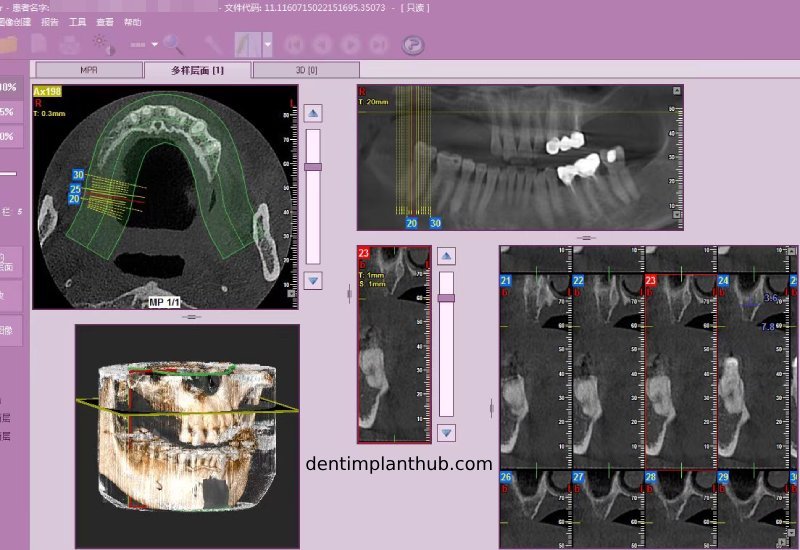

Screenshot of patient's CT on March 14, 2024